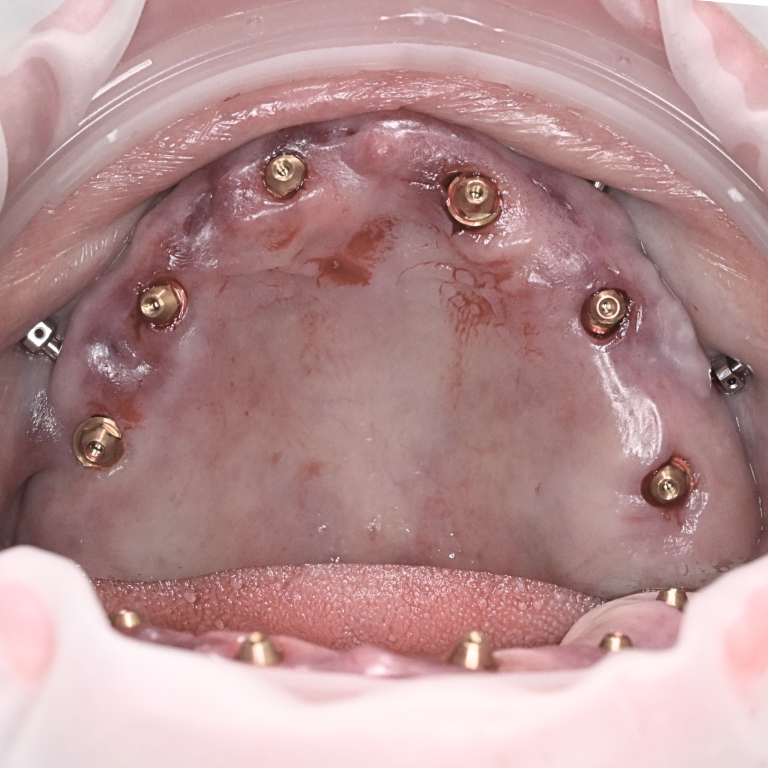

微創導航植牙應用不會受限在手術範圍的大小,小至單顆植牙,多至單顎 All on 4/6/X 都可以使用。整個手術過程都需要搭配 NAVIDENT 4 數位導航才能確保精準和安全。

微創導航 All on 6